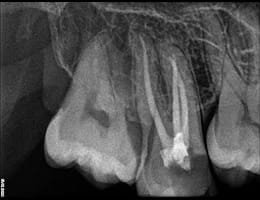

The cleaned canals are filled with a biocompatible material, usually gutta-percha, to seal them and prevent future infection.

After the root canal is completed, the temporary filling is removed, and a permanent restoration, such as a crown, is placed to protect and restore the tooth’s function.

gutta core

Superior Filling Materials

GuttaCore: For the best sealing of the root canal system, we use GuttaCore, which provides a 3D fill and superior adaptation to the canal walls.

Lateral Condensation: This technique allows for a dense and well-sealed root canal filling, preventing reinfection and promoting long-term success.